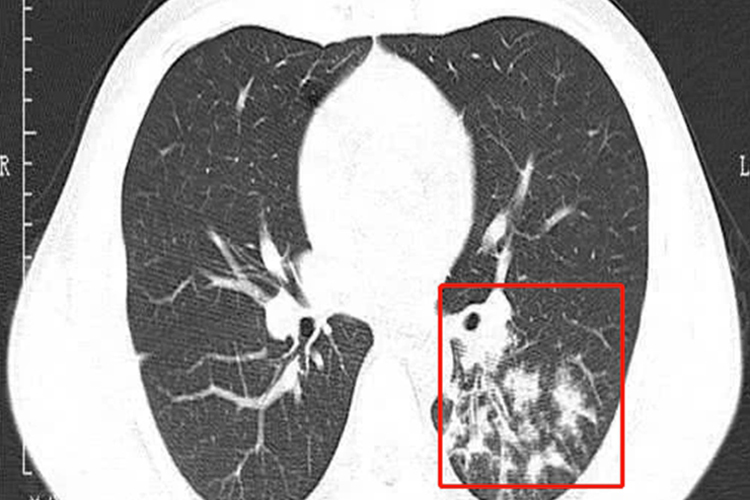

小叶性肺炎的病变实质是什么

小叶性肺炎的病变实质是化脓性炎症,这种炎症涉及到肺组织的微观结构改变、炎症细胞的活动以及病原体的作用等多个方面。患者应积极配合医生进行治疗,并定期进行复查。•小...